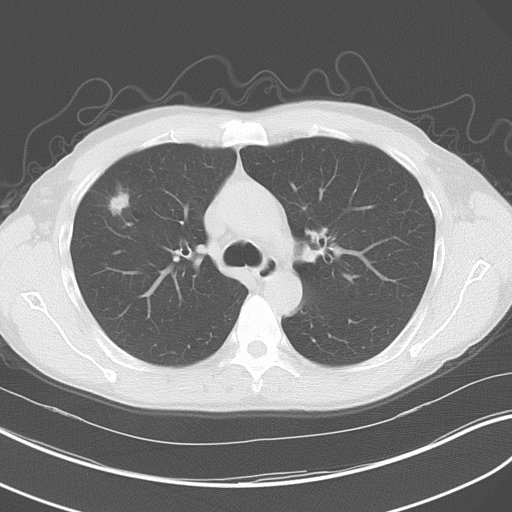

The UC Lung Cancer Center was proactive in adopting the United States Preventive Services Task Force2 (USPSTF) 2013 recommendation for low-dose computed tomography (CT) for lung cancer screening. “We formed a multidisciplinary Lung Cancer Screening Program consisting of specialists in thoracic surgery, pulmonary medicine, medical oncology, radiation oncology, chest radiology and lung pathology,” says Elsira Pina, DO, pulmonary lung cancer specialist and professor of medicine. The UC Lung Cancer Center follows national guidelines for screening: annual low-dose CT screening for adults aged 55 to 79 years who have at least a 30 pack-year (e.g. 1 pack per day for 30 years, or two packs per day for 15 years) smoking history.

The critical advantage of low-dose CT screening is that lung cancers are detected at an earlier, more curable stage (largely, stage 1), “when detection results in both increased survival and a decreased mortality,” says Dr. Pina. The landmark study, The National Lung Screening Trial (NLST), demonstrated a 20% reduction in mortality from lung cancer with low-dose CT screening compared to chest x-ray. The USPSTF recommendation came after extensive review of the risks and benefits of low-dose CT scans in detecting lung cancer and lowering mortality rates, and after examination of concerns about potential drawbacks, such as radiation dose from serial imaging, false-positive findings and overdiagnosis.3-7

Patients who enroll in the Center’s screening program receive an initial low-dose CT scan and, depending on the results, are advised to continue annual screening or further workup. If more diagnostic procedures such as endobronchial ultrasounds and/or navigational bronchoscopy are necessary, they are performed by pulmonologists skilled in advanced diagnostic procedures. All results are reviewed by the multidisciplinary lung cancer team in a weekly lung cancer tumor board. Dedicated nurse coordinators guide patients through the screening process and coordinate all facets of care. The Center also works closely with the patient’s primary care physician, to ensure appropriate follow-up.